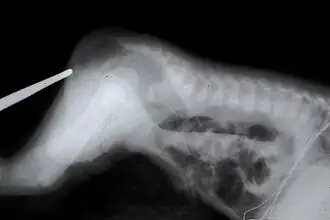

Atresie van de uitwendige gehoorgang

- Een atresie van de uitwendige gehoorgang is het ontbreken van een luchthoudende toegang tot het middenoor. Voor het betreffende oor is dan sprake van een maximaal geleidingsverlies.